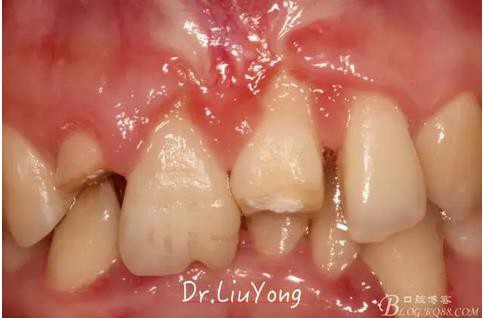

上唇系帶的附著,如上圖:

通過(guò)根向復(fù)位瓣術(shù)解決上唇系帶的附著問(wèn)題

上唇系帶手術(shù)后一周拆線,如上圖